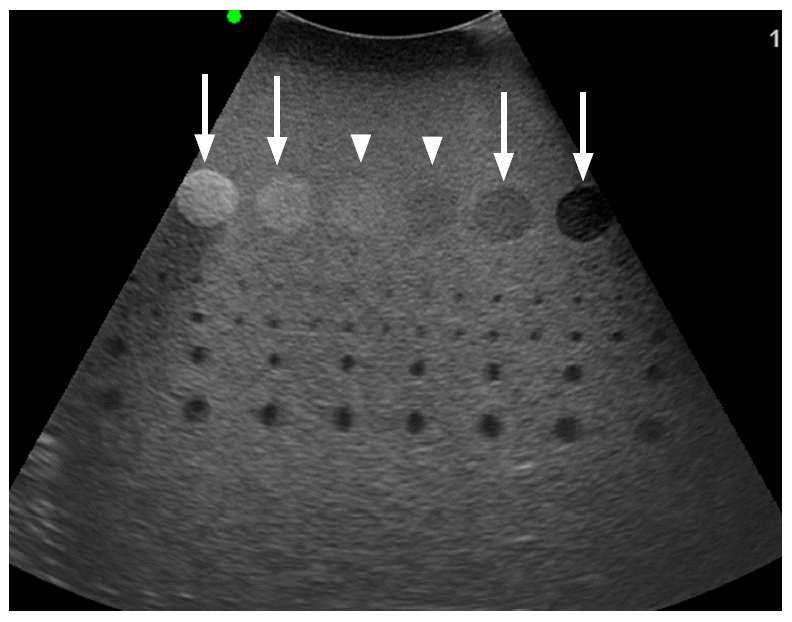

Szürkeskálás kép

Ezen a képen egy modellen láthatjuk a szürkeskála szemléltetését. Egyöntetű szürke háttéren láthatunk különböző árnyalatú kerek foltokat, melyek a világosabb felől a sötétebb irányába haladnak. A szürke háttér a viszonyítási alap, úgy ahogy a valós vizsgálat során, a vizsgált szerv állományának az árnyalata. Az olyan foltok, melyek hasonló árnyalatúak isoechogénként kerülnek leírásra, amelyek világosabbak hyperechogének és amik sötétebbek hypoechogének.